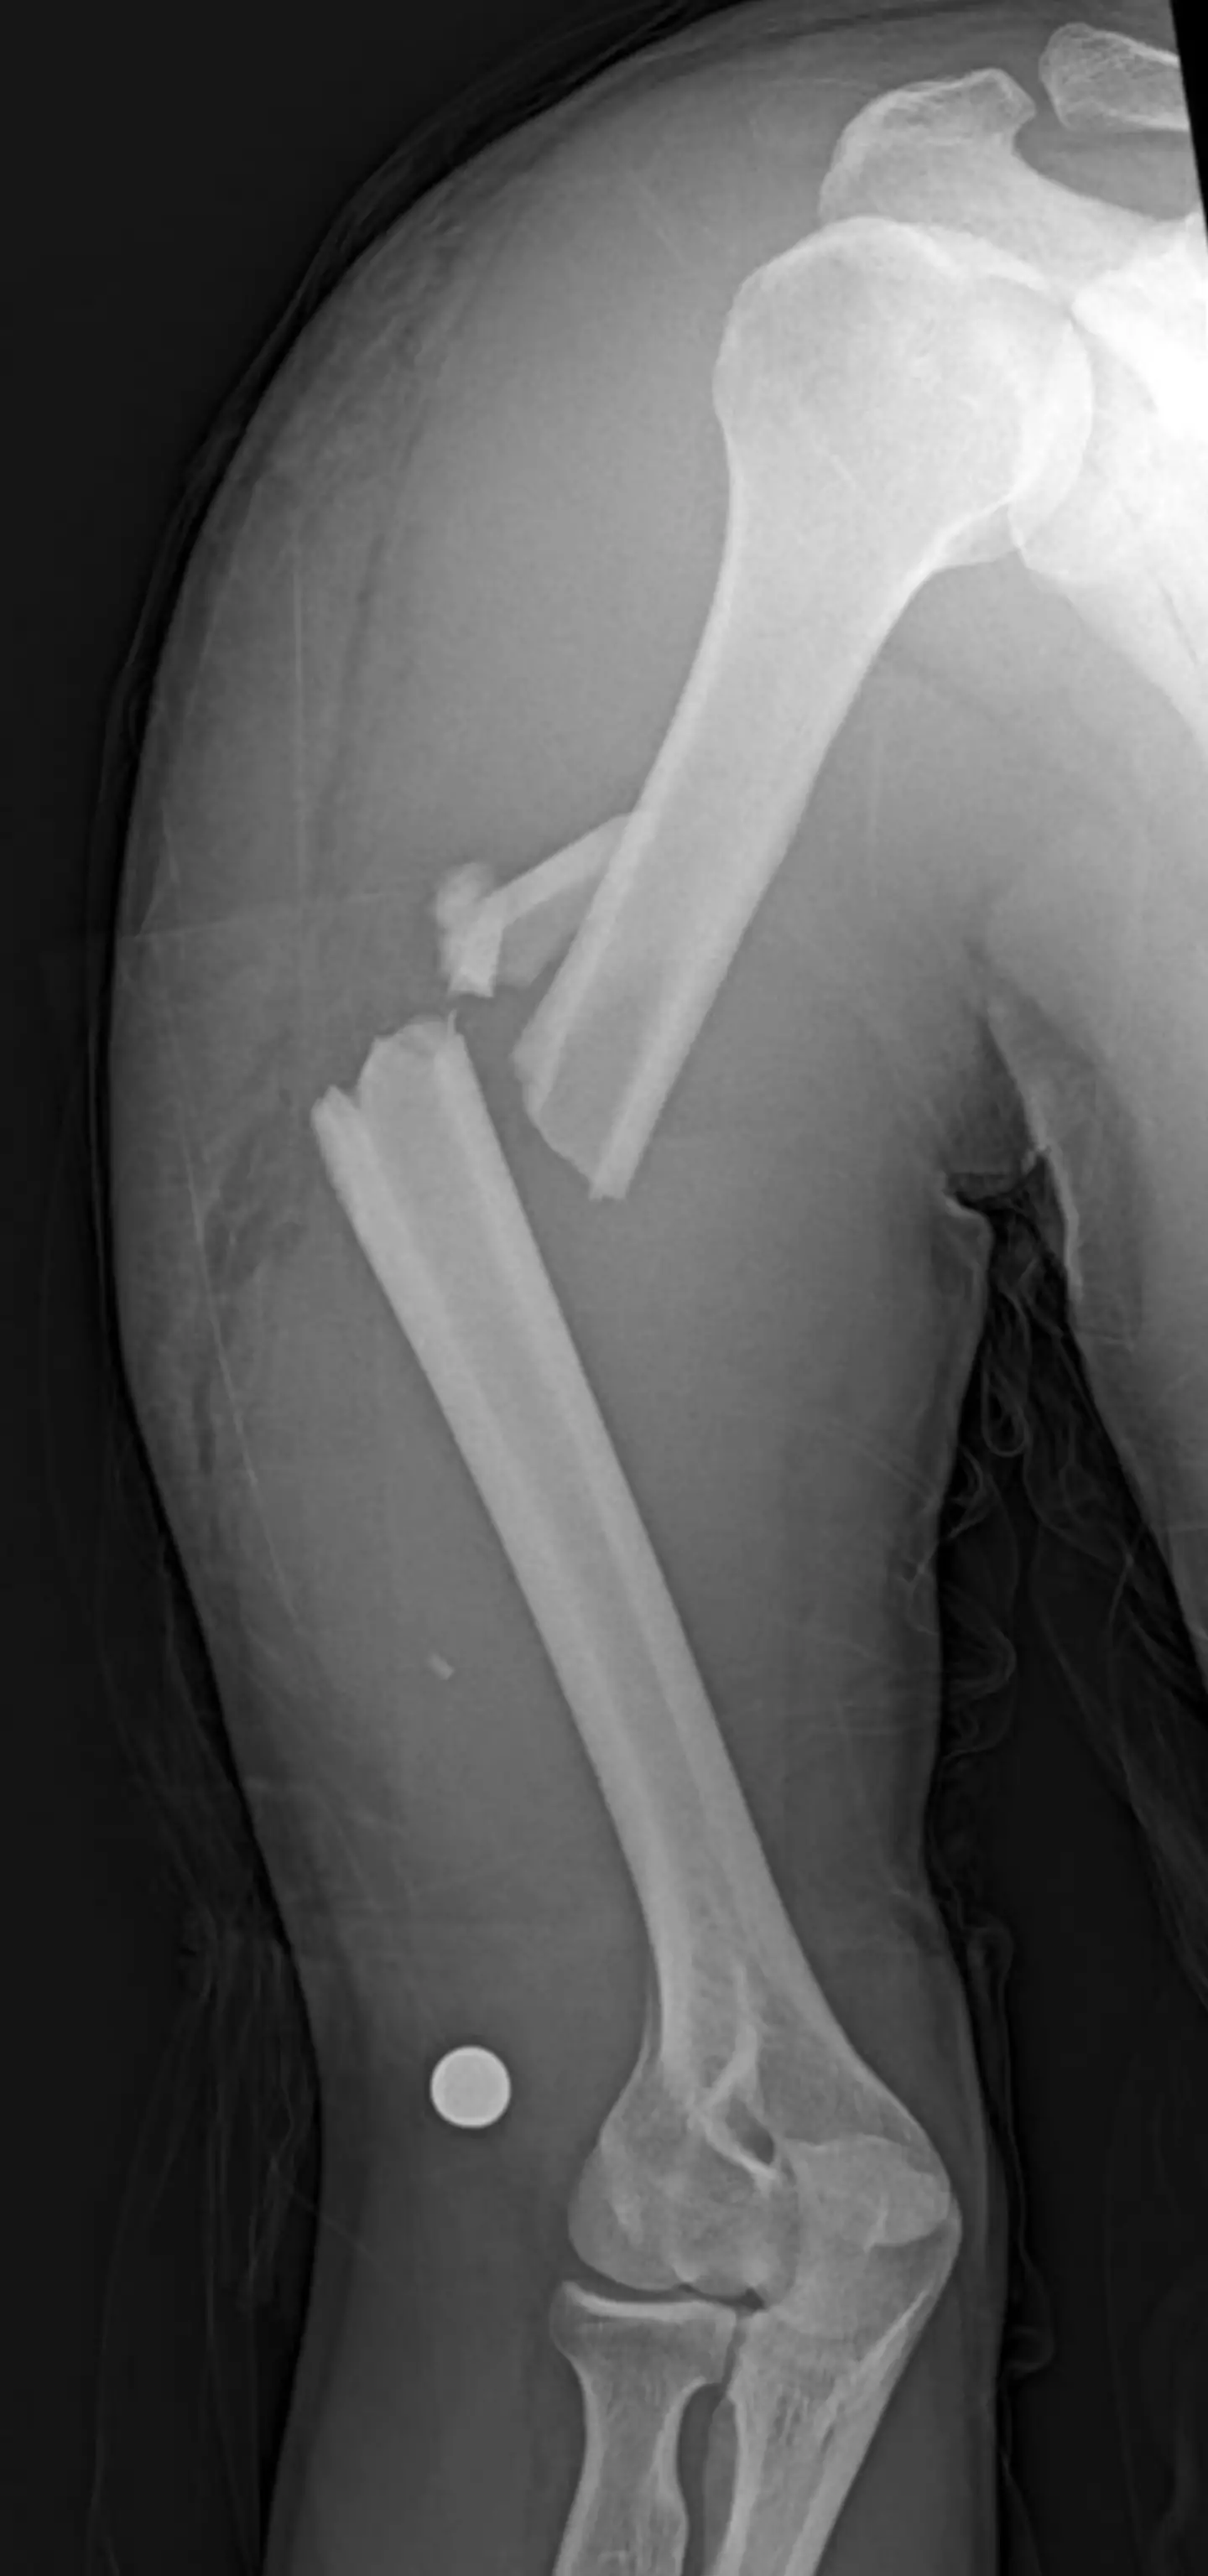

Well, it largely seems to be folks who have come close to breaking a bone - e.g. dislocations, having to have staples, hockey pucks to the face - boasting of how their bones stayed strong. Others ask if they get extra points for breaking other people's bones, while their own skeleton remains unharmed.

And then there are people sharing pictures of themselves in casts, bidding goodbye to the community of no broken bones.